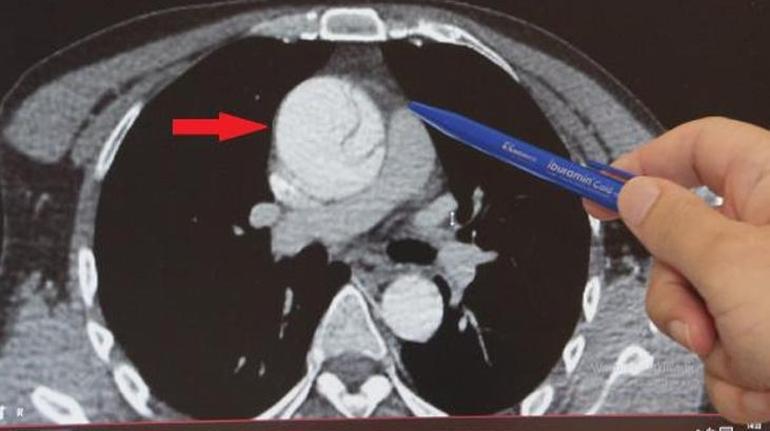

Daha önce hiçbir sağlık sorunu olmayan 41 yaşındaki Mustafa Turan, birkaç hafta önce arkadaşlarıyla ayak üstü sohbet ederken “Göğsümde yırtılırcasına bir ağrı başladı” diyerek fenalaştı ve acile kaldırıldı. Kalp ekosu çekildi çeşitli tahliller yapıldı ancak her şey normal görünüyordu. Ağrılarının midesinden olabileceği düşünüldü ve gerekli tedavileri verilip taburcu edildi. Şiddetli ağrıları ertesi gün de devam eden Turan, gece 02:00 sularında Göztepe Süleyman Yalçın Şehir Hastanesi acil servisine başvurdu. Acildeki doktorun şüphelenmesi üzerine tekrar EKO çekildi, abdominal aort anevrizması (AAA) nedeniyle karın bölgesinden geçen aort damarında yırtık olduğu tespit edildi. Normalde 2 santim çapında olması gereken aort damarı anevrizma (balonlaşma) nedeniyle genişleyerek neredeyse 3 katına ulaşmış, damar duvarında yırtığa neden olmuştu. Hayati riski olduğu anlaşılan Turan, kalp damar cerrahisi ekibi tarafından acilen ameliyata alındı.

Göztepe Süleyman Yalçın şehir Hastanesi Kalp Damar Cerrahisi Klinik Şefi Prof. Dr. Ebuzer Aydın, “Arkadaşlarıyla konuşurken böyle bir boğazında düğümlenme şikayeti oluyor. Bunun üzerine ambulansla acile geliyor. Tetkikleri yapılıyor, daha çok mide şikayetleri düşünülerek o yönde tetkikler yapılıyor ve tedavisi verilip gönderiliyor. Ağrıları geçmeyince tekrar acile geliyor, acildeki doktor arkadaşlarımızın dikkati ve özeni sayesinde ayrıntılı tetkik yapılıyor ve bu sırada aort diseksiyonu olduğu görülüyor. Bize konsülte edildi ve hızlı bir şekilde ameliyathanemizi ayarladık, acilen ameliyata aldık” dedi.

Aort anevrizmasının çoğunlukla sessiz ilerlediğini kaydeden Prof. Dr. Aydın, genellikle başka tetkikler yapılırken tesadüfen teşhis edilen hastalıkta en önemli şeyin, aort damarında yırtık meydana geldikten sonra kaybedilen her 1 saat için ölüm riskinin yüzde 1 artması olduğunu vurguladı ve şu bilgileri verdi: “Acil ameliyatla, elektif (planlı) ameliyat arasında ölüm riski açısından, ameliyattaki diğer riskler ve hastaya getirdiği başka tehlikeler açısından çok ciddi farklar var. Her 1 saat için ölüm riski yüzde 1 artar. Bu hastalar çoğunlukla kanama ve getirdiği bir takım diğer komplikasyonlarla kaybedilir. Planlı ameliyatlarda ölüm riski yaklaşık yüzde 5 iken diseksiyon meydana geldiğinde bu risk yüzde 20-25’lere kadar çıkabiliyor. Yani planlı bir anevrizma ameliyatı ile diseksiyon ameliyatı arasında 4-5 kat fark var”